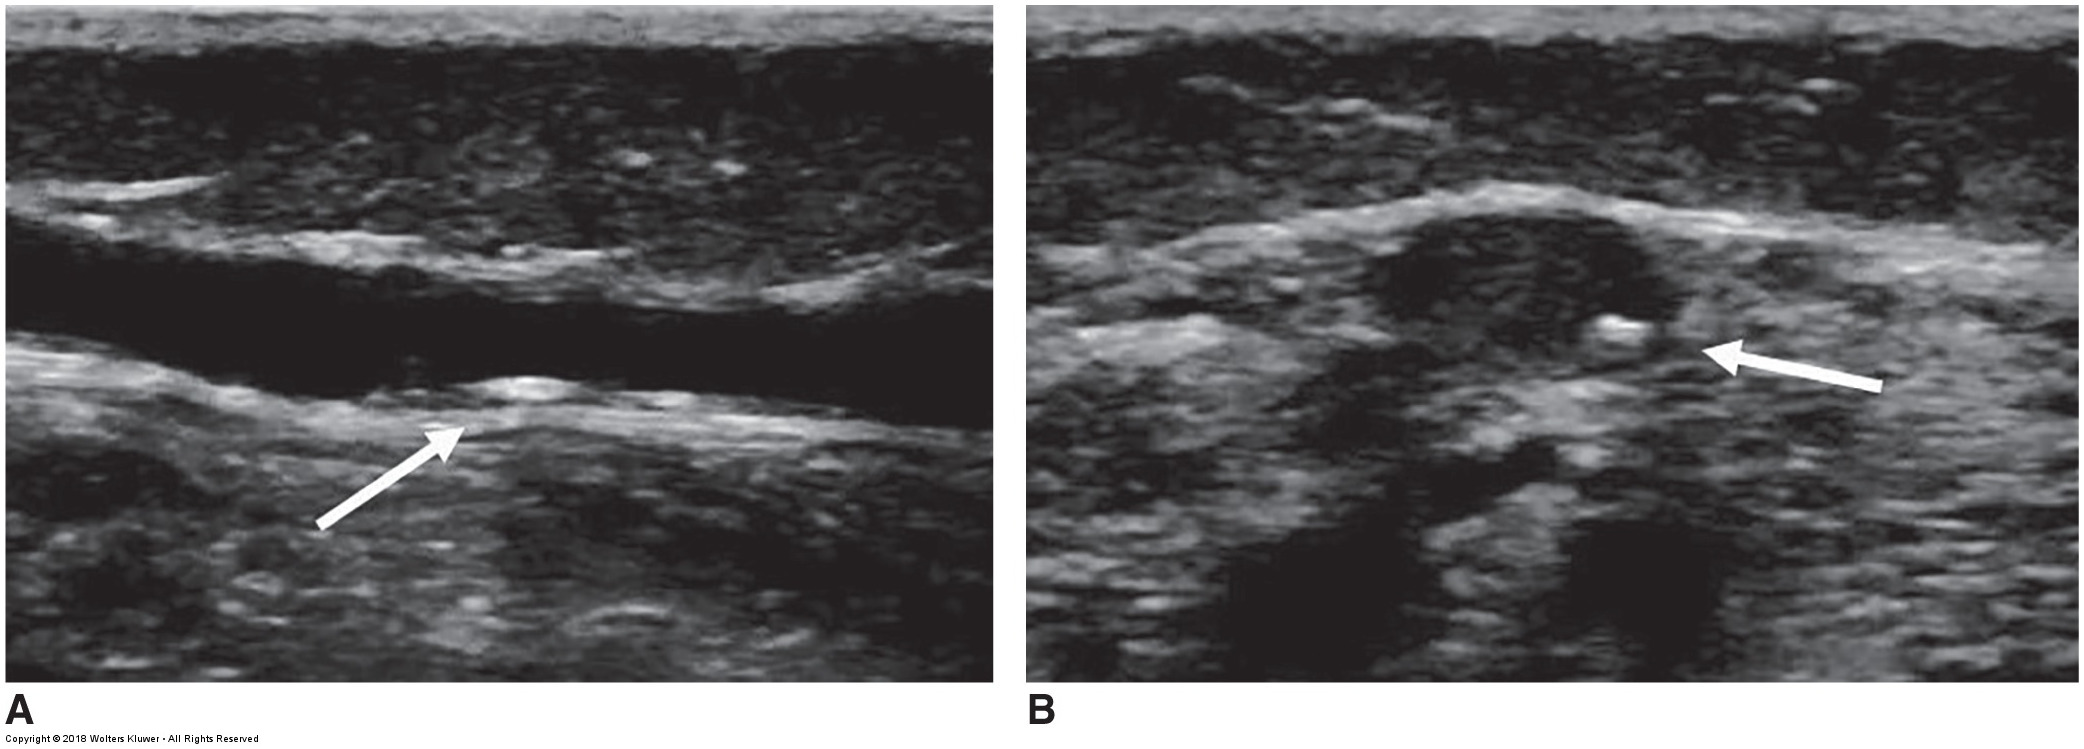

ultrasound of the SSV with wall calcification

ultrasound image of a frozen valve leaflet